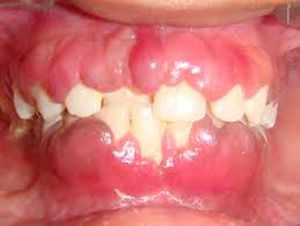

Gingival hyperplasia due to some drug? Phenytoin?

Gingival hyper plasia patient may take dilantin for epilepsy or have drugs make the enlargement

Aml